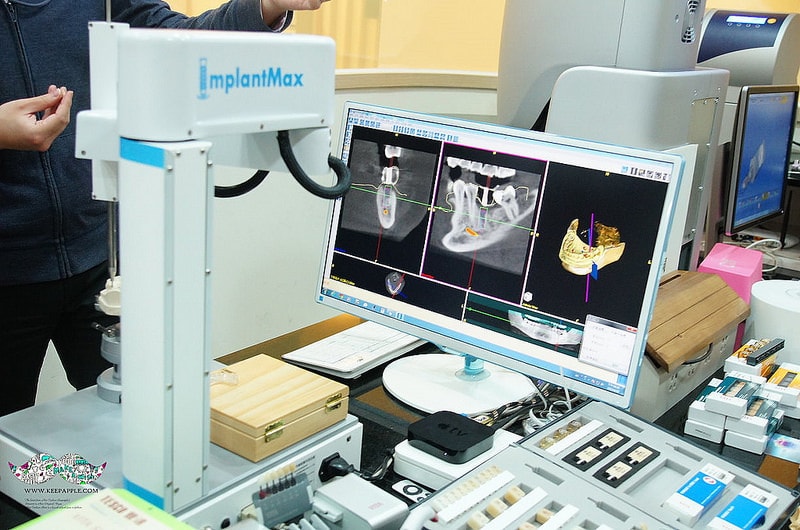

悅庭牙醫診所的3D導航植牙系統也是一大特色

主要就是運用這台GPS導航植牙( i – Max 寰視導引植牙系統)的機器

多虧台大醫工所的研發製造

讓醫生可以更精準的處理病患植牙的正確位置

口腔狀況與細節都可以輕鬆掌握

將手術傷口面積可以降到最小的範圍

這套系統最重要的目的就是讓牙醫師在術前先進行過一次模擬植牙手術

利用電腦3D定位精準演算分析出植牙位置與角度

看要從哪個角度、深度進行植牙~

在經過預先演練以後牙醫師在真正動手術時,

既能節省時間又能大幅增加植牙成功率

加上悅庭牙醫的植體是使用來自瑞典的諾保科

是穩定且安全的全球植牙系統。

對有植牙需求的病人來說可以說是一大福音啊!